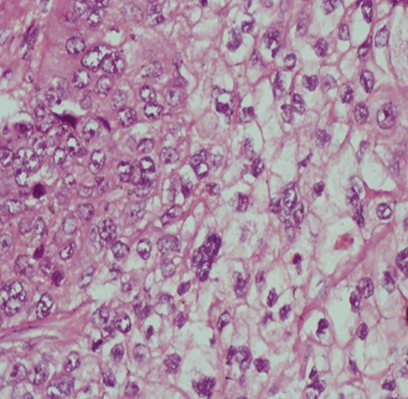

Figure 2. Photomicrograph showing moderately differentiated sebaceous

epithelial cells with abundant foamy to clear cytoplasm. Haematoxylin and eosin

stain. X400 magnification.

done and histopathologic examination of sections of the tumour showed a

malignant epithelial neoplasm composed of moderate to markedly pleomorphic

cells disposed in nests, cords and sheets invading a desmoplastic stroma and

the sclera. The cells have moderately pleomorphic vesicular nuclei, prominent

nucleoli and foamy to clear cytoplasm with distinct cell membranes (figures 1 and 2). Features are in